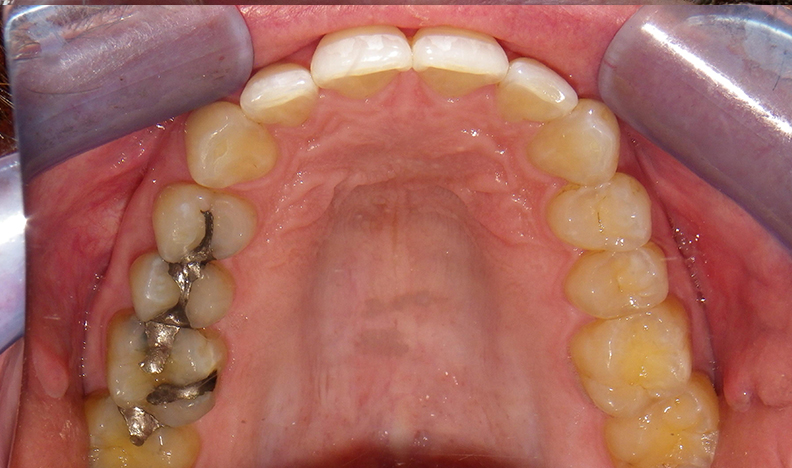

In contrast, the bad airway photo is the mouth of a patient who has no airway problems, breathes through the nose and rests his tongue against the roof of his mouth. This arch is a broad U-shape with well-aligned teeth.